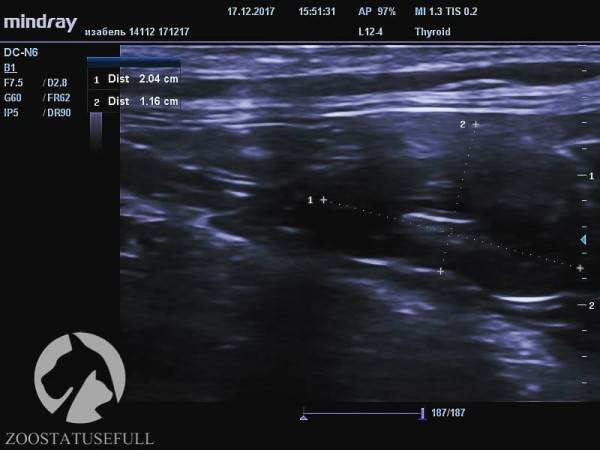

Мочевой пузырь кошки Изабель на УЗИ

Здоровая почка кошки Изабель (обратите внимание на размер, указан в см)

Больная почка кошки Изабель

На снимках, используемых в этой статье, кошка Изабель — являющаяся показательным примером того, что случится с органами мочевыделительной системы «спинальника», если животному не опорожнять мануально мочевой пузырь. Изабель утратила функцию произвольного мочеиспускания в возрасте котёнка, после чего целый год жила в приюте для бездомных животных, где не знали о необходимости мануально опорожнять мочевой пузырь кошке, которая не может осуществить диурез самостоятельно. За самостоятельное мочеиспускание воспринималось протекание по каплям на фоне переполнения.

Постоянное переполнение и перерастяжение мочевого пузыря превратили когда-то упругий «шарик» (мочевой пузырь) в растянутую атоничную «тряпочку». Качественно мануально опорожнять этот мочевой пузырь сейчас — очень тяжело даже опытным ветеринарным врачам.

Но самое главное — воспалительный процесс, возникший в мочевыделительной системе на фоне «неотжимания» привёл к заболеванию, а потом и к «гибели» одной из почек. На снимках можно увидеть разницу между функционирующей почкой и нефункционирующей.

Это очень важно, обратите на это внимание — Изабель осталась с одной функционирующей почкой, потому что ее мочевой пузырь не опорожняли мануально, а не наоборот.